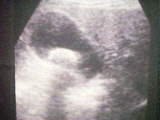

腹部エコー検査

エコー検査は超音波を使った検査でお腹にゼリーを塗って検査します。胆石の数や種類、胆嚢壁の異常など得られる情報が多く、手軽に何回も繰り返して検査することができます。左のエコー写真には1個、右の写真には2個胆石が写っています。